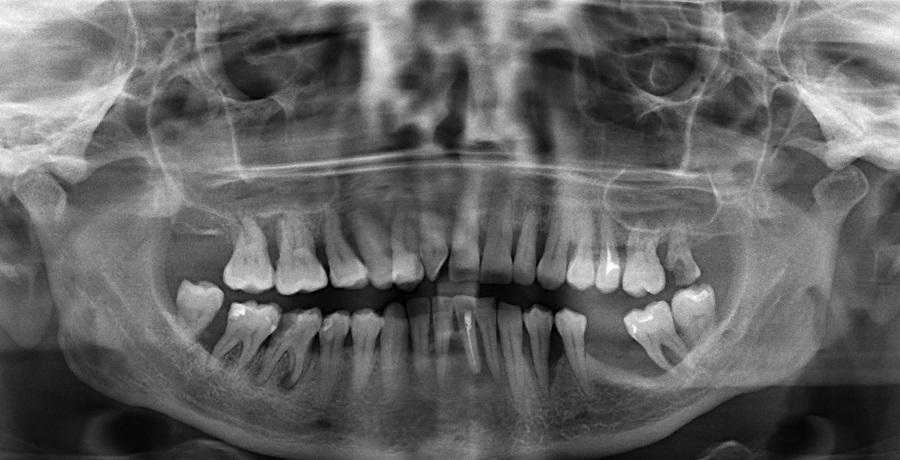

Истончение кости челюсти видно на снимке

Костная ткань постоянно обновляется. За этот процесс отвечают два типа клеток — остеобласты и остеокласты. Клетки-остеобласты создают новую ткань, а клетки-остеокласты разрушают старую. В молодой возрасте эти процессы находятся в балансе, а в более старшем процессы резорбции (разрушения) начинают преобладать. Это происходит со всеми костями, поэтому к пожилому возрасту масса костей и их плотность у человека снижается. После 50 лет потеря костной ткани составляет примерно 2 % в год.